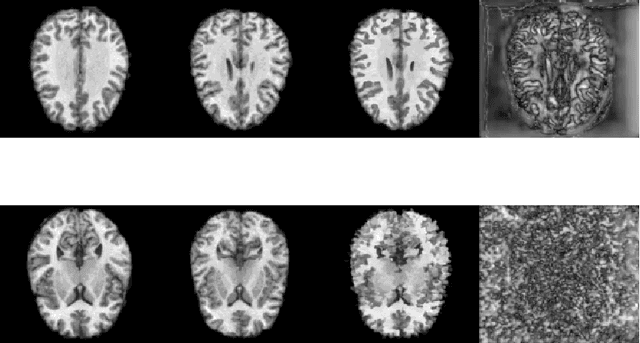

Quantification of uncertainty in deep-neural-networks (DNN) based image registration algorithms plays an important role in the safe deployment of real-world medical applications and research-oriented processing pipelines, and in improving generalization capabilities. Currently available approaches for uncertainty estimation, including the variational encoder-decoder architecture and the inference-time dropout approach, require specific network architectures and assume parametric distribution of the latent space which may result in sub-optimal characterization of the posterior distribution for the predicted deformation-fields. We introduce the NPBDREG, a fully non-parametric Bayesian framework for unsupervised DNN-based deformable image registration by combining an \texttt{Adam} optimizer with stochastic gradient Langevin dynamics (SGLD) to characterize the true posterior distribution through posterior sampling. The NPBDREG provides a principled non-parametric way to characterize the true posterior distribution, thus providing improved uncertainty estimates and confidence measures in a theoretically well-founded and computationally efficient way. We demonstrated the added-value of NPBDREG, compared to the baseline probabilistic \texttt{VoxelMorph} unsupervised model (PrVXM), on brain MRI images registration using $390$ image pairs from four publicly available databases: MGH10, CMUC12, ISBR18 and LPBA40. The NPBDREG shows a slight improvement in the registration accuracy compared to PrVXM (Dice score of $0.73$ vs. $0.68$, $p \ll 0.01$), a better generalization capability for data corrupted by a mixed structure noise (e.g Dice score of $0.729$ vs. $0.686$ for $\alpha=0.2$) and last but foremost, a significantly better correlation of the predicted uncertainty with out-of-distribution data ($r>0.95$ vs. $r<0.5$).